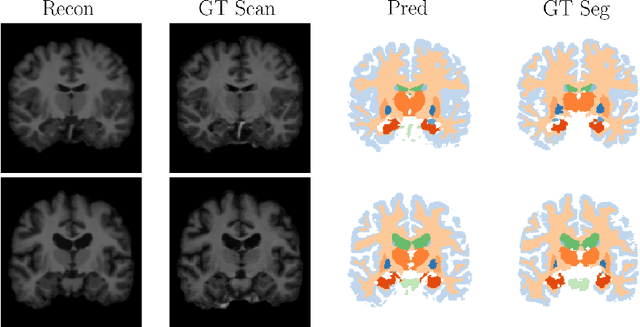

Abstract:Deep neural networks are powerful tools for biomedical image segmentation. These models are often trained with heavy supervision, relying on pairs of images and corresponding voxel-level labels. However, obtaining segmentations of anatomical regions on a large number of cases can be prohibitively expensive. Thus there is a strong need for deep learning-based segmentation tools that do not require heavy supervision and can continuously adapt. In this paper, we propose a novel perspective of segmentation as a discrete representation learning problem, and present a variational autoencoder segmentation strategy that is flexible and adaptive. Our method, called Segmentation Auto-Encoder (SAE), leverages all available unlabeled scans and merely requires a segmentation prior, which can be a single unpaired segmentation image. In experiments, we apply SAE to brain MRI scans. Our results show that SAE can produce good quality segmentations, particularly when the prior is good. We demonstrate that a Markov Random Field prior can yield significantly better results than a spatially independent prior. Our code is freely available at https://github.com/evanmy/sae.